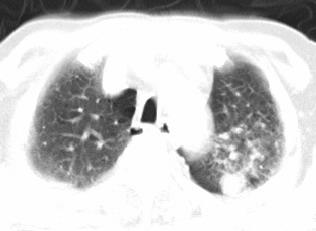

以下是引用xianxianzhongyi在2008-4-20 14:44:00的发言:[br]本人愚见:次病例短短两月的时间,呈现如此大面积实变,病变增长过于迅速,此其一。其二,病变在动脉早期既有明显强化。其三,左上叶后段及下叶背段多叶受累。其四,肺门及纵隔内未见明显肿大的淋巴结。估计层面较厚段支气管显示不清。 诊断:炎性实变可能性大。

以下是引用光影相伴在2008-4-20 14:39:00的发言:[br]支持:1)左侧中央型肺癌伴左肺上叶阻塞性肺炎。、[br] 2)双侧少量胸腔积液。